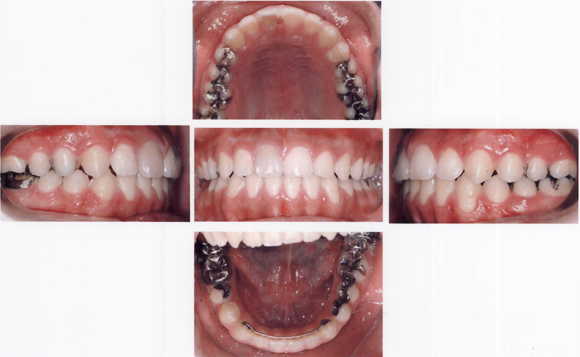

CASE3 上顎が出ているケース

術前

術後